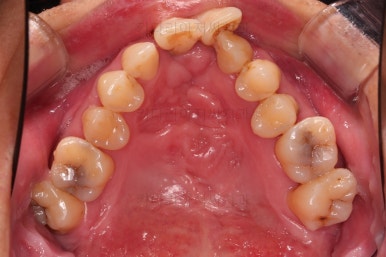

1. 초진 시 입안의 모습

부산구순구개열교정 키다리아저씨치과에 처음 내원하셨을 당시의 입안의 모습입니다.

이번 환자분도 이와 같은 일반적인 특징이 그대로 나타나 있었습니다.

양측성 구순구개열이었으므로 작은 앞니(대문니와 송곳니 사이)가 양쪽 다 결손이었고, 또 다른 이유로 아래 앞니도 1개 없는 상태였습니다.

3. 초진 시 X-ray 분석

기본적인 파노라마 사진으로 치아 갯수, 뿌리 상태 등을 파악하고 CT 영상을 통해 골결손 부위, 비강 및 기도의 형태까지 파악해 줍니다.

윗니 2개, 아랫니 1개가 결손이었기 때문에 보철로 추가적으로 치아를 해 넣을지의 여부가 매우 중요했는데요

✅ 추가로 치아를 해 넣지 않고, 현재 치아만으로 교합을 맞추기로 했습니다.

결손 부위의 잇몸뼈의 상태가 썩 좋지 못하며, 대문니 2개의 상태도 장기적으로는 좋지 못할 것으로 예상되어 굳이 주위 치아에 힘을 많이 가하면서까지 공간을 확보하고 치아를 해 넣을 필요는 없다고 판단되었고요.

대신, 치아의 갯수가 위아래가 맞지 않아서 생기는 약간의 애매한 교합 부분은 감수하기로 했습니다.